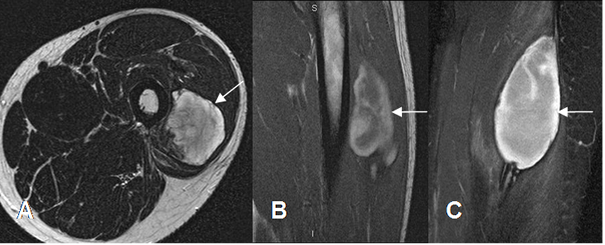

Fig 62. Hematoma muscular.

A: RM axial en T2, B: RM sagital en T1 y C: RM coronal en STIR. Colección heterogénea en el músculo vasto externo, por hematoma muscular. Es hiperintenso en T1, por el contenido de deoxihemoglobina, indicando evolución subaguda.